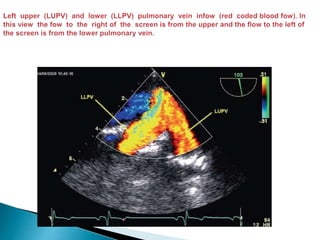

 The left upper pulmonary vein (LUPV), which enters the LA just

lateral to the LAA from an anterior to posterior trajectory, is identified

by withdrawing slightly and turning the probe to the left.

 The left lower pulmonary vein (LLPV) is then identified by turning

slightly farther to the left and advancing 1 to 2 cm. The LLPV enters

the LA just below the LUPV, courses in a more lateral to medial

direction, and is less suitable for Doppler quantification of pulmonary

venous blood flow velocity being nearly perpendicular to the

ultrasound beam.

 In some patients, the LUPV and LLPV join and enter the LA as a

single vessel